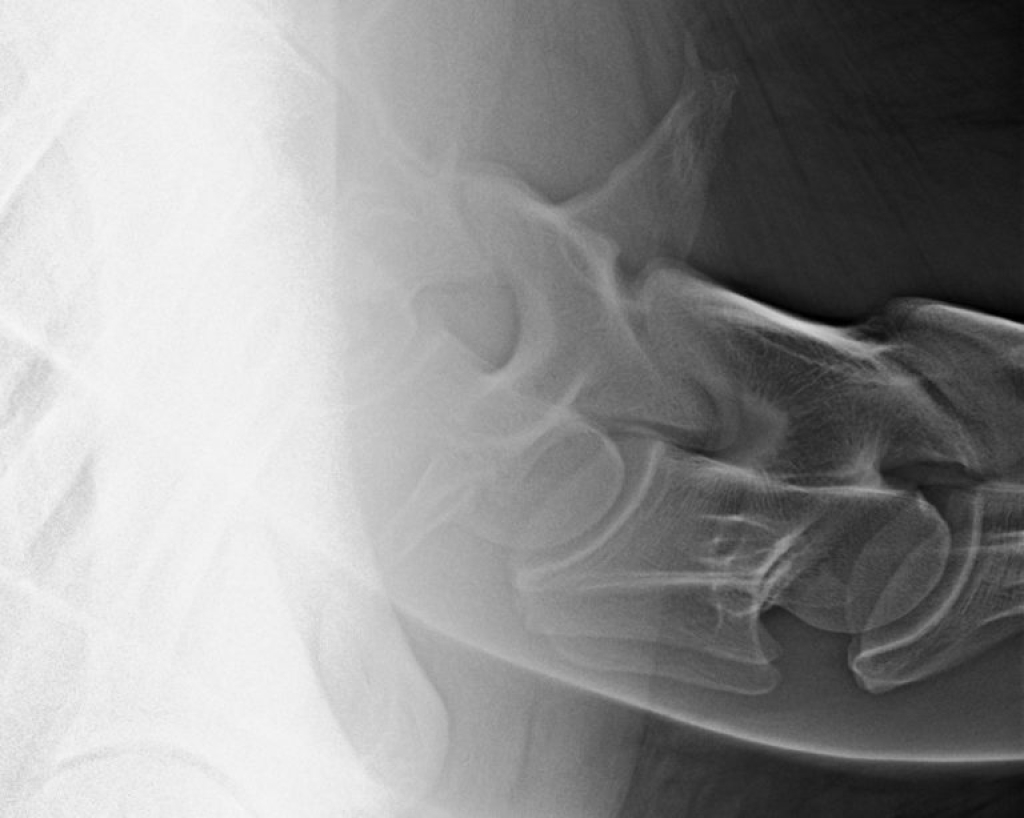

Afwijkende beelden

Links: Breuk in het facetgewricht

Rechts: Uitprojectie breuk facetgewricht

Breuk in het facetgewricht

Uitprojectie breuk facetgewricht